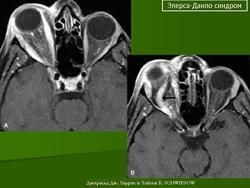

4. Кифосколиотический тип.

Наследуется по аутосомно-рецессивному типу. Основные диагностические критерии: генерализованная гипермобильность суставов, выраженная мышечная гипотония при рождении, прогрессирующий (с рождения) сколиоз, кифоз, хрупкость склер разрывы глазного яблока. Дополнительные диагностические критерии: хрупкость тканей, иногда атрофичные рубцы, склонность к кровоизлияниям, разрывы артерий, марфоноидный фенотип, микрокорнеа, рентгенологически выявляемая выраженная остеопения, положительный семейный анамнез ( в том числе больные сибсы).

Следует отметить, что наличие трех основных критериев является основанием для предположения диагноза и требует лабораторного обследования. Причем мышечная гипотония может быть очень выраженной и обусловливает задержку моторного развития. Выраженный сколиоз приводит к тому, что во второй-третьей декаде жизни больные теряют способность передвигаться самостоятельно. Хрупкость тканей глаза является причиной разрыва глазного яблока при малейшей травме. Согласно последним данным, тяжелые глазные осложнения встречаются гораздо реже, чем предполагалось ранее. При этом типе СЭД дефект в синтезе коллагена заключается в изменении фермента лизил-гидроксилазы, которая катализирует гидроксилирование боковых лизиновых цепей, необходимых для перекрестных связей между соседними коллагеновыми молекулами при формировании тройной спирали.